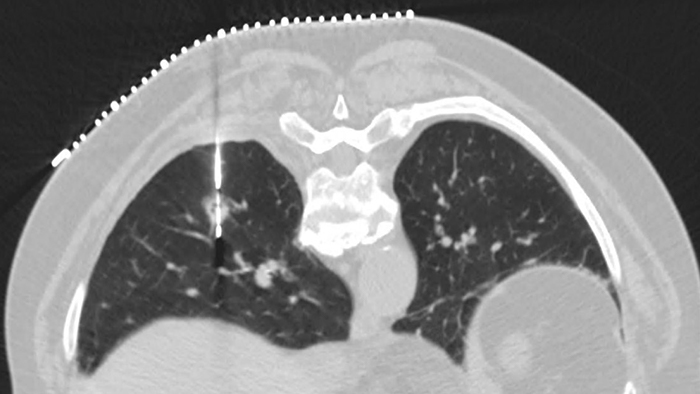

Overcome cardiac imaging challenges

Motion-free cardiac imaging improves image quality at high heart rates

ContinueAdvanced motion-compensation reconstruction for motion-free cardiac scanning with improved coronary analysis